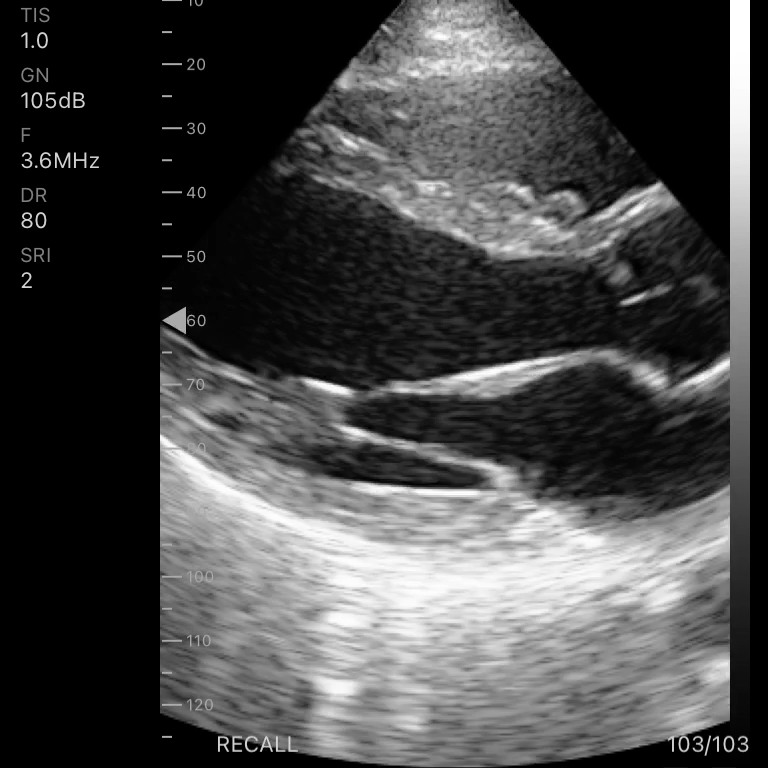

| Modo de escaneo | B, B/M, Color, PW |

Modos de escaneo: B, B/M, Color, PW

Profundidad de pantalla: 90 – 190 mm

Exámenes básicos y control de flujo cardíaco o vascular en entornos clínicos y extrahospitalarios.